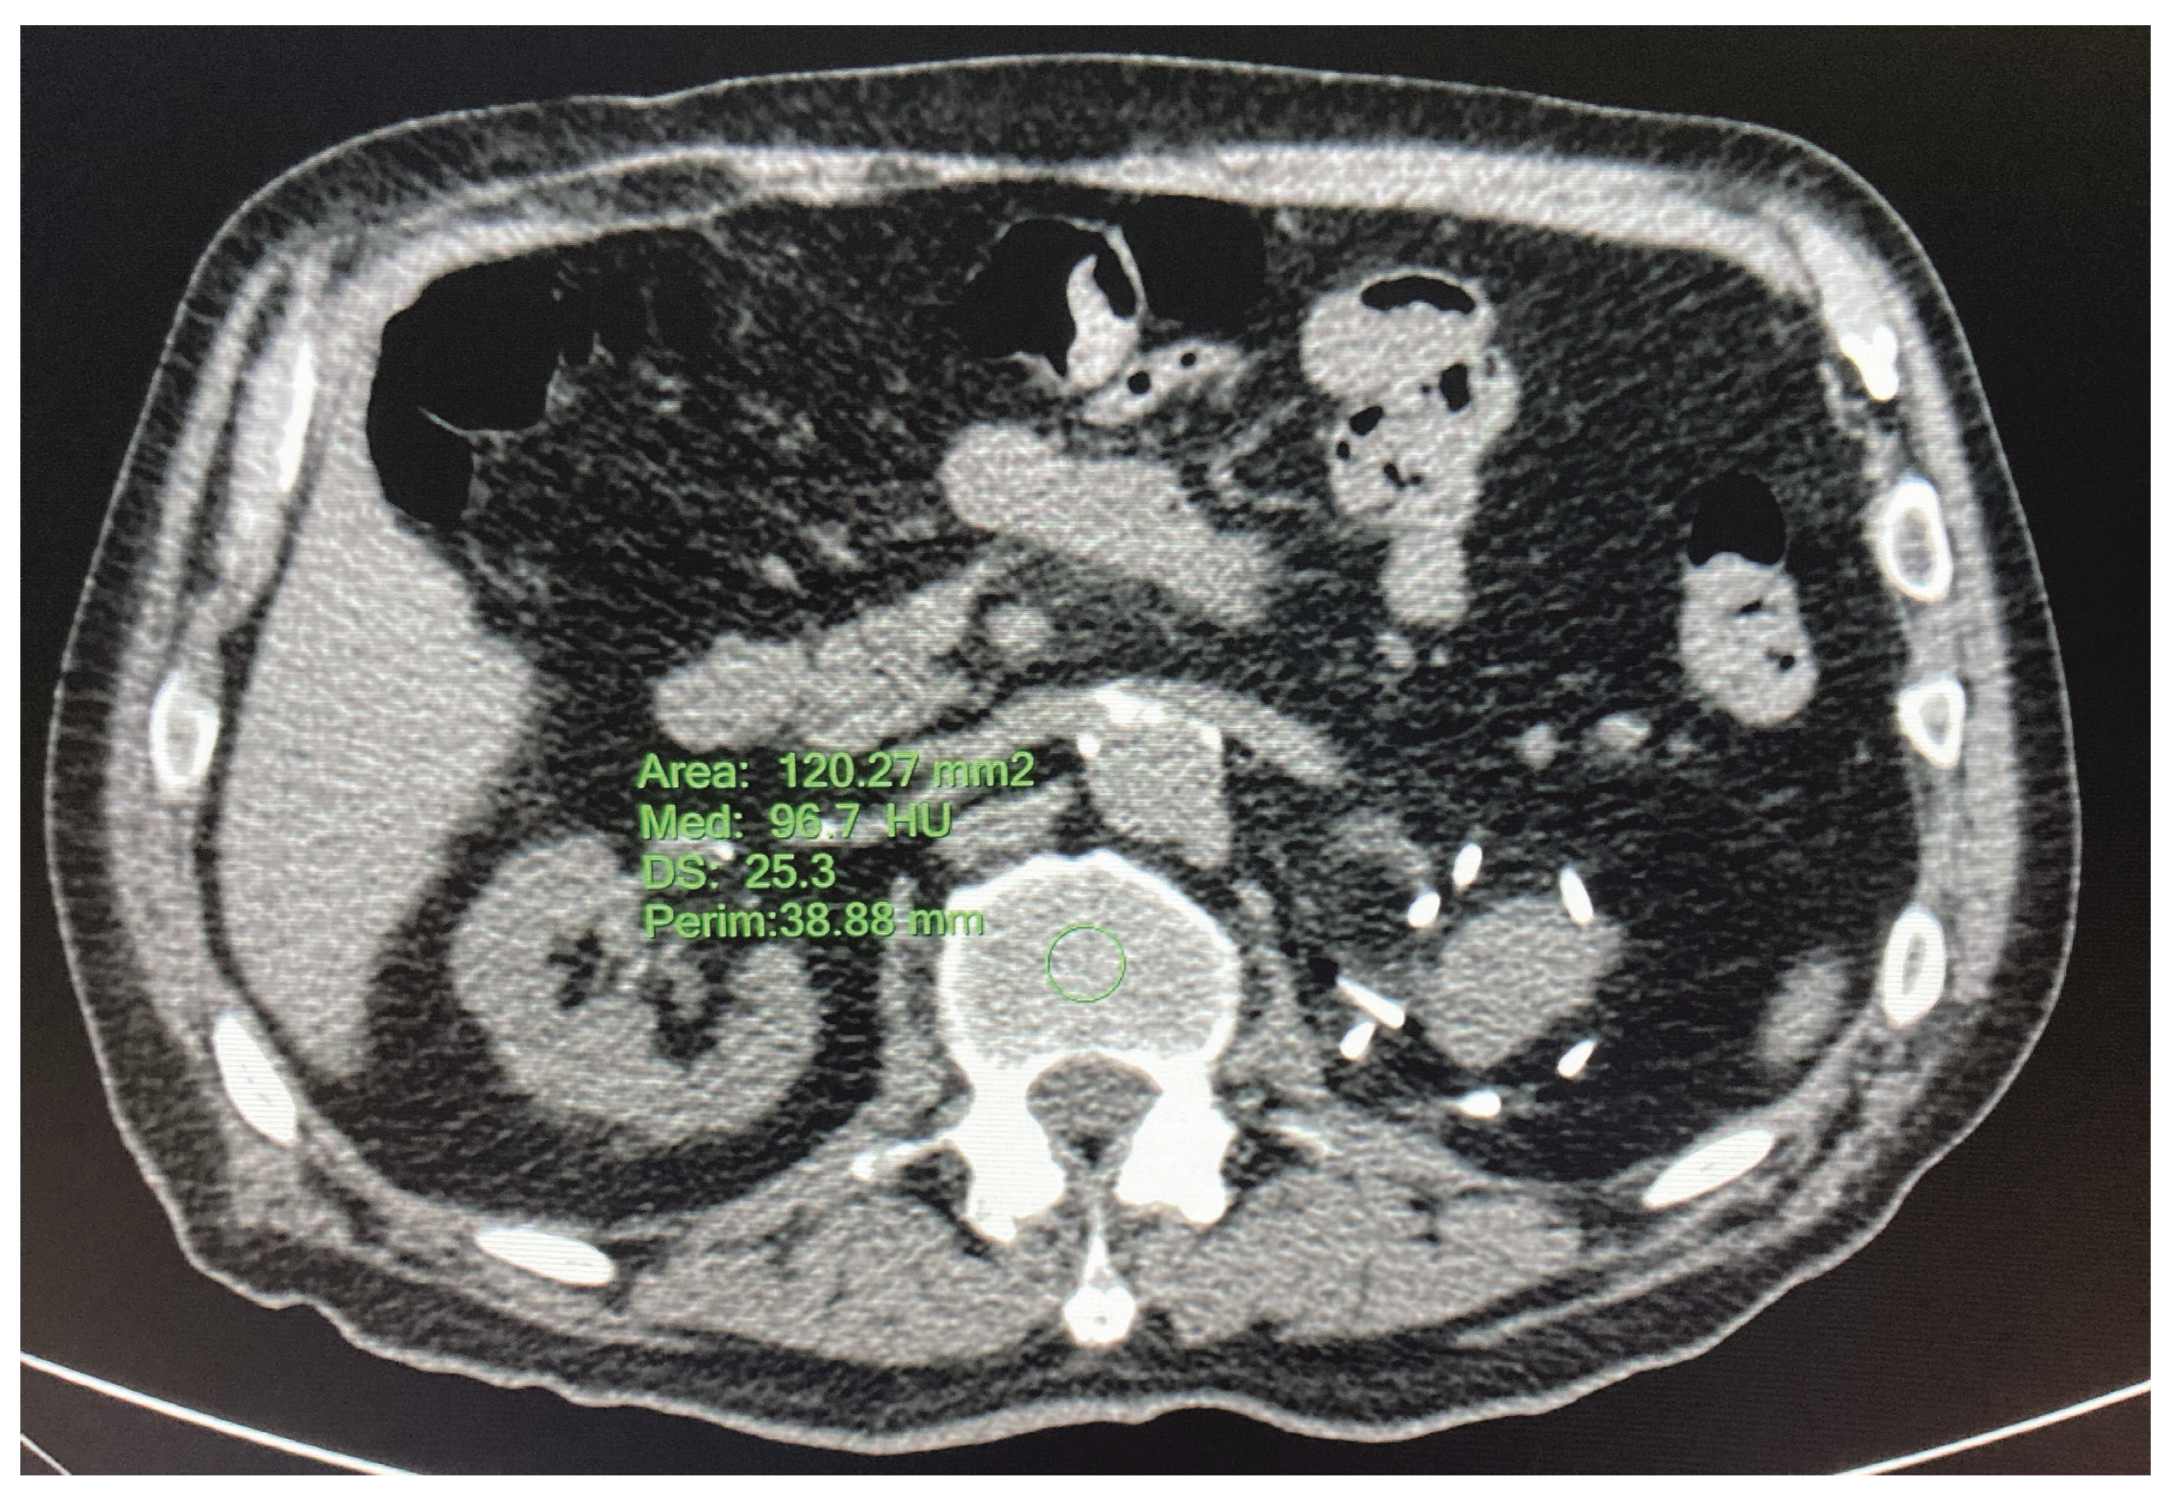

2.4. Statistical Analysis